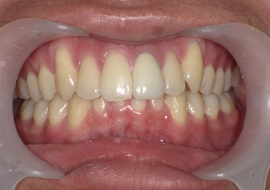

症例6

Before

After

| 主訴 | 噛み合わせが気になる |

|---|---|

| 年齢 | --- |

| 治療 期間 |

約2年11ヶ月 |

| 治療 内容 |

インビザラインコンプリヘンシブ 右上6番・左上6番ALLセラミッククラウン |

| 治療費 | ¥1,116,000(税込)/調整料含む |

| 治療のリスク | 歯を動かすことで、歯茎が下がるリスクある。 矯正終了後は、リテーナーを使用し、後戻りを防ぐ必要がある。 |